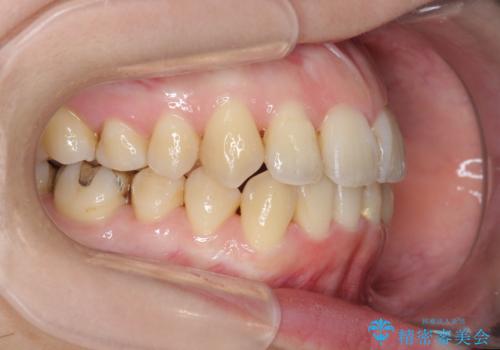

前歯のがたつき すれ違い咬合のマウスピース矯正治療

- 前歯のがたつきや歯の角度、矯正治療を希望され来院されました。

仕事の都合で、ワイヤー矯正を行うことが難しくマウスピース矯正であれば可能、という希望でした。

下顎が前にある咬合関係を可及的に咬合移動で改善し、IPR、下顎3前歯の仕上げで行うマウスピース矯正を計画します。

他院では、「マウスピース矯正では治らない。」と言われ当院に相談に見えましたが、マウスピースで達成できるゴールを模索することで矯正治療を行えることがあります。